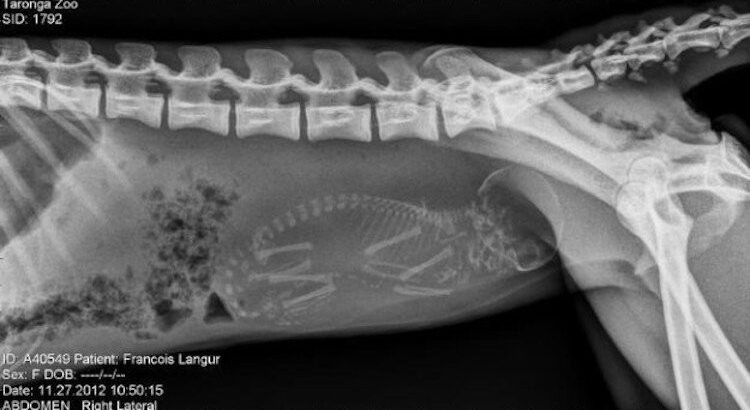

Le saviez-vous ? Les singes sont des mammifères de l'ordre des primates. Malgré d’évidentes ressemblances avec nous les bipèdes, les scientifiques ont mis de nombreux siècles à prouver le lien étroit qui existe entre les singes et l’homme.

Après une période de gestation variant de 6 à 9 mois selon certaines races, les femelles donnent naissance principalement à un petit à la fois. A peine sorti, le bébé s'accroche au pelage de sa mère, tête, dort et crie. (Toute ressemblance…)

Le baby-sitting est une affaire de famille. En plus du père, ce sont souvent les frères et sœurs qui s'occupent des petits.